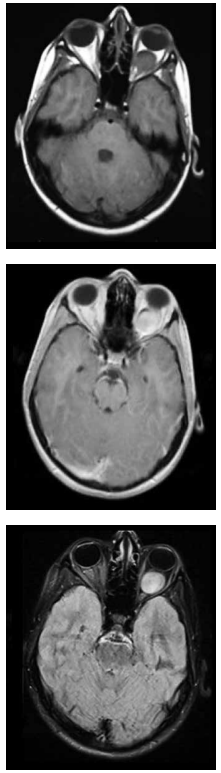

Criança de 3 anos, com quadro clínico de náuseas

e vômitos há 3 meses. Realizou Tomografia Computadorizada (TC) de crânio com lesão expansiva

hiperdensa no quarto ventrículo causando hidrocefalia. Na Ressonância Magnética (RM) de crânio

observou-se lesão originando no assoalho do quarto

ventrículo, com realce heterogêneo, com áreas de

necrose e calcificação e com extensão as cisternas e

aos foramens adjacentes. Considerando a principal

hipótese diagnóstica, pode-se afirmar que: